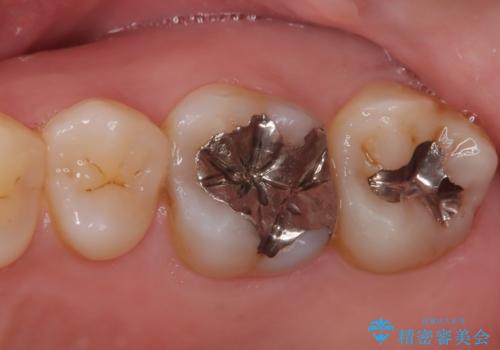

- メタルフリーを主訴に来院されました。

歯牙の破折を防ぐために、セラミッククラウンにて修復しています。